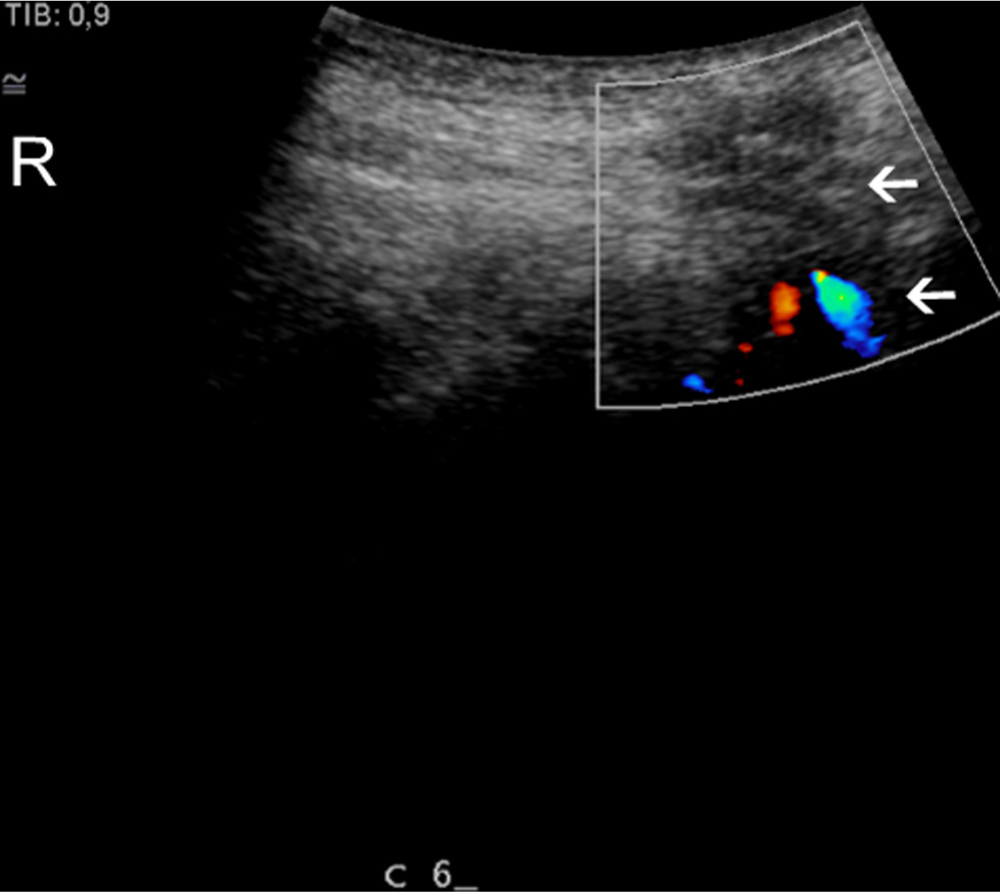

Longitudinal colour, Doppler scan of a patient. C6 spinous processes. Arrows identify homogeneity and blood vessels in the intraspinous ligament. R, rostral.